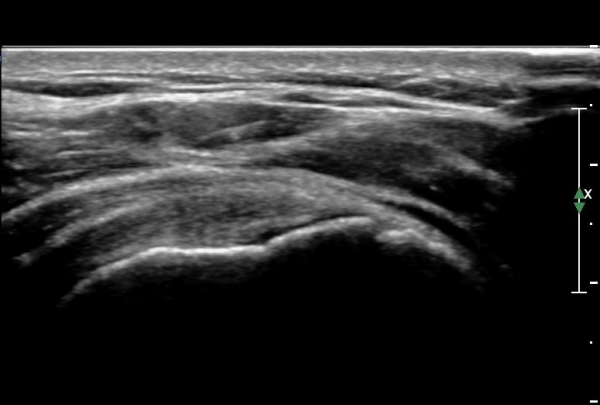

¿À±¸µ¹±â°ßºÀÀδë Á¾´Ü¸é°Ë»ç¿¡¼­ ÀÎ´ë ½ÉÃþ¿¡ ¼ö¾×Àú·ù°¡ °üÂûµÊ(»çÁø 1, 2)

ÀÌ´Â Ãæµ¹ÁõÈıºÀ» ¾Ï½ÃÇÏ´Â ¼Ò°ßÀÓ.